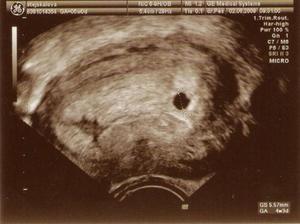

Náš Tomíšek má sestřičku Terinku :o)